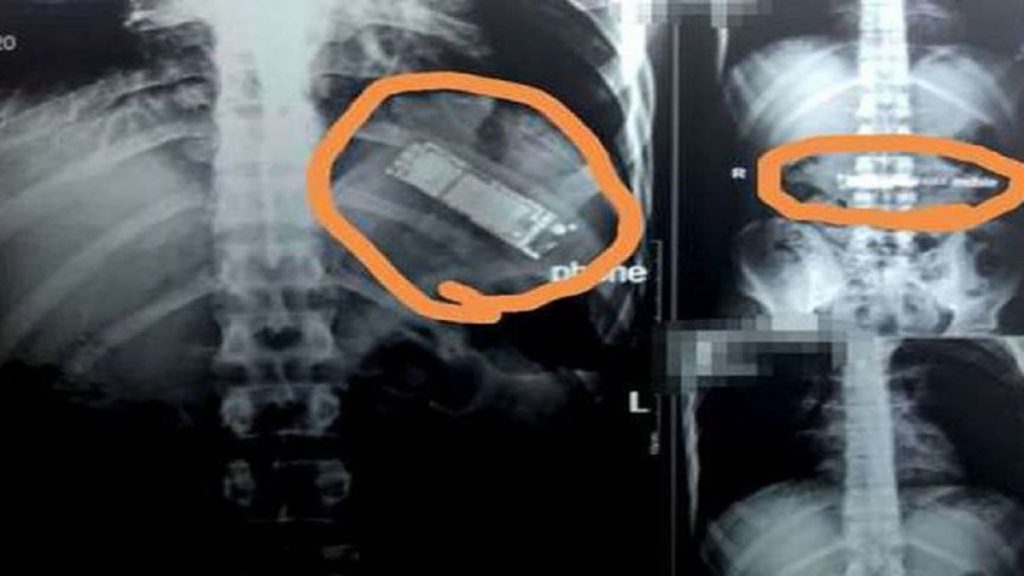

মিসরের রাজধানী কায়রোর একটি হাসপাতালে এক যুবকের পেটে আল্ট্রাসনোগ্রাম করে রিপোর্ট দেখে চিকিৎসকদের চোখ কপালে।

আস্ত একটি মোবাইল ফোন ২৮ বছরের ওই যুবকটির পেটের ভেতর। গত সাত মাস ধরেই এটি পেটের মধ্যেই ছিল। খবর গালফ নিউজের।

দক্ষিণ কায়রোর আল ওয়াটান নামে ওই বেসরকারি হাসপাতালের চিকিৎসক ডা. মো. আল জহোর বলেন, প্রথমে টিউমার মনে করে অস্ত্রোপচারের জন্য আল্ট্রাসনোগ্রাম করা হয়। কিন্তু এতে দেখা যায়, আস্ত একটি মোবাইল ফোনসেট।